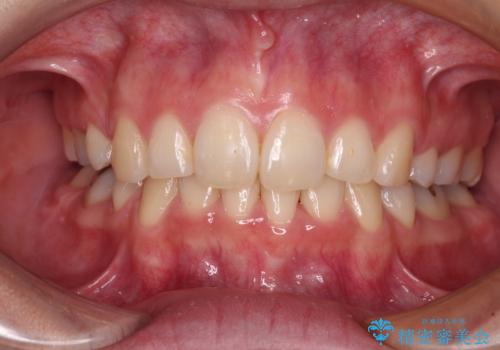

八重歯と形の悪い前歯 矯正治療とセラミック治療